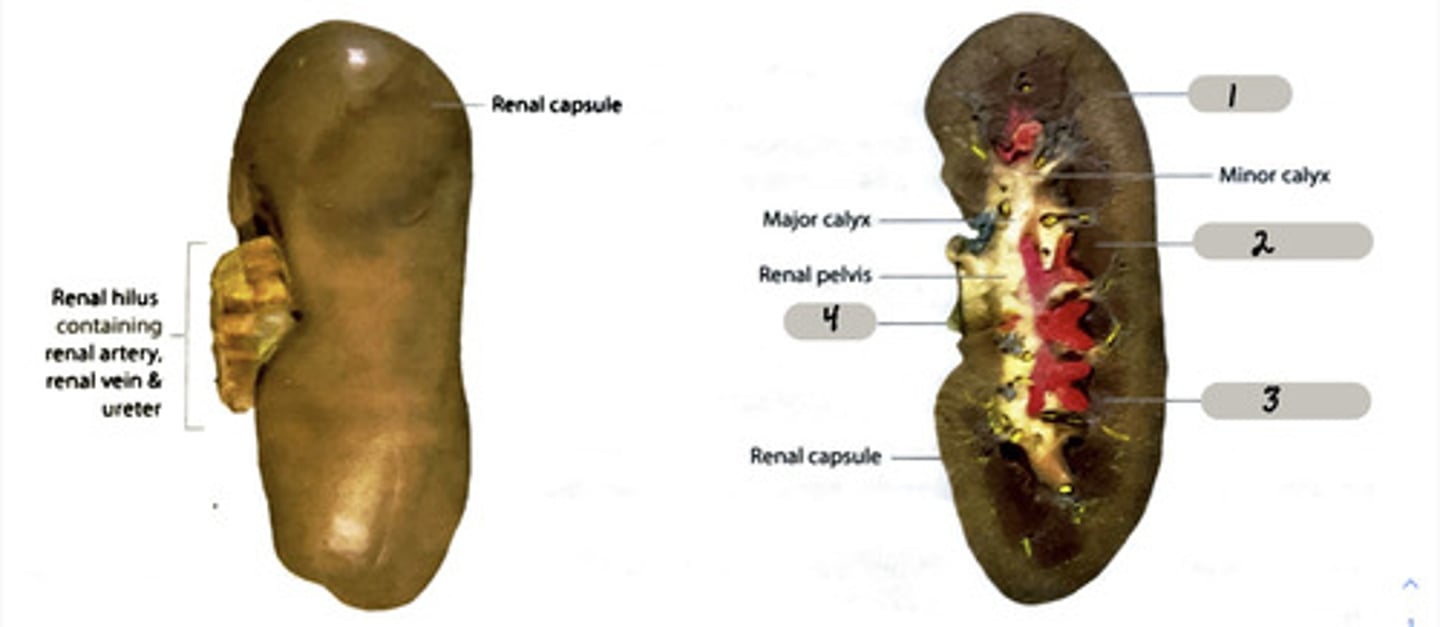

Urinary-kidneys, ureters, urinary bladder, uretha

form urine in order to maintain water balance salt balance, pH, and nitrogenous waste levels in the blood

renal pyramid

2

renal column

3

cortex

outer layer of the kidney

ureter

A duct leading from the kidney to the urinary bladder.

nephron

the functional unit of the kidney

Adrenal gland